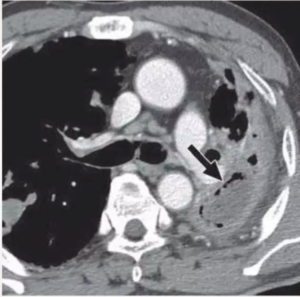

PERICARDITIS

• ⁠ ⁠Tuberculosis may predispose to the development of bronchogenic carcinoma by local mechanisms (scar cancer)

• ⁠ ⁠Carcinoma may lead to reactivation of TB, both by eroding into an encapsulated focus and by affecting the patient’s immunity.

TUBERCULOUS PERICARDITIS